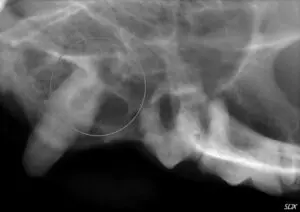

Detailed examination and dental radiographs (x-rays) are the best way to diagnose tooth resorption. Sometimes, resorptive lesions are obvious with visual examination. A red, fleshy lesion at the gum line (seen above left) or degradation on the tooth itself can sometimes be seen on visual exam. However, when tooth resorption is below the gum line, dental radiographs are necessary to diagnose the location and type of resorption. Pictured to the left, a cat tooth shows resorption of the tooth root (circled) only on x-rays. The tooth otherwise appeared normal.